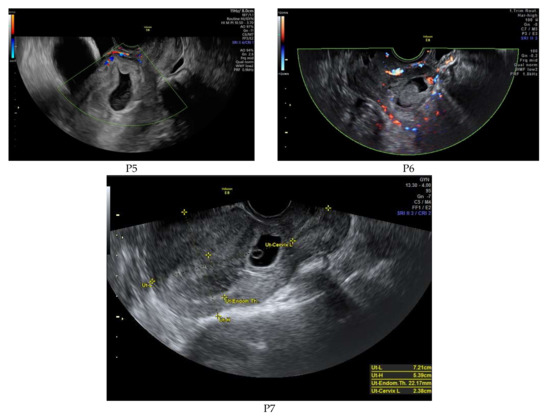

| P5 | 4579 | 5w + 6d | Type 2 | 1.Intramuscular methotrexate injection 2. Uterine artery embolization 3.Suction evacuation | No complications |

| P6 | 70,373 | 6w + 5d | Type 1 | 1. Intramuscular methotrexate injection 2. Uterine artery embolization 3. Suction evacuation | No complications |

| P7 | 46,317 | 6w + 2d | Type 2 | 1. Intramuscular methotrexate injection 2. Uterine artery embolization 3. Suction evacuation | No complications |

| P5 | 4 | absent | normal | Not measured | 8 | 29.4 |

| P6 | 3.8 | absent | increased | 4 | 23 | 19.7 |

| P7 | 3.5 | present | increased | 5 | 28 | 21 |